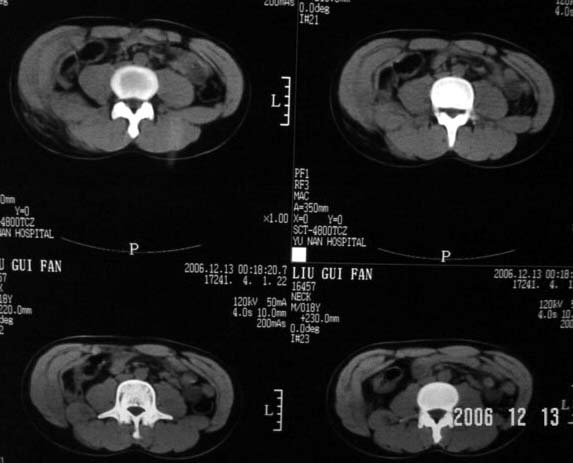

以下是引用守望可可西里在2006-12-13 22:25:00的发言:[br]再明确不过的右侧髂骨骨折,呵呵,这回总不会被忽悠了!

以下是引用liuyue在2006-12-13 23:45:00的发言:[br]右侧髂骨骨折伴局部软组织及腹壁肿胀

以下是引用xiaoniu在2006-12-13 22:22:00的发言:[br]右侧髂前上嵴骨折伴局部腹壁血肿。[br][br][本贴已被 xiaoniu 于 2006-12-13 22:24:13 修改过]